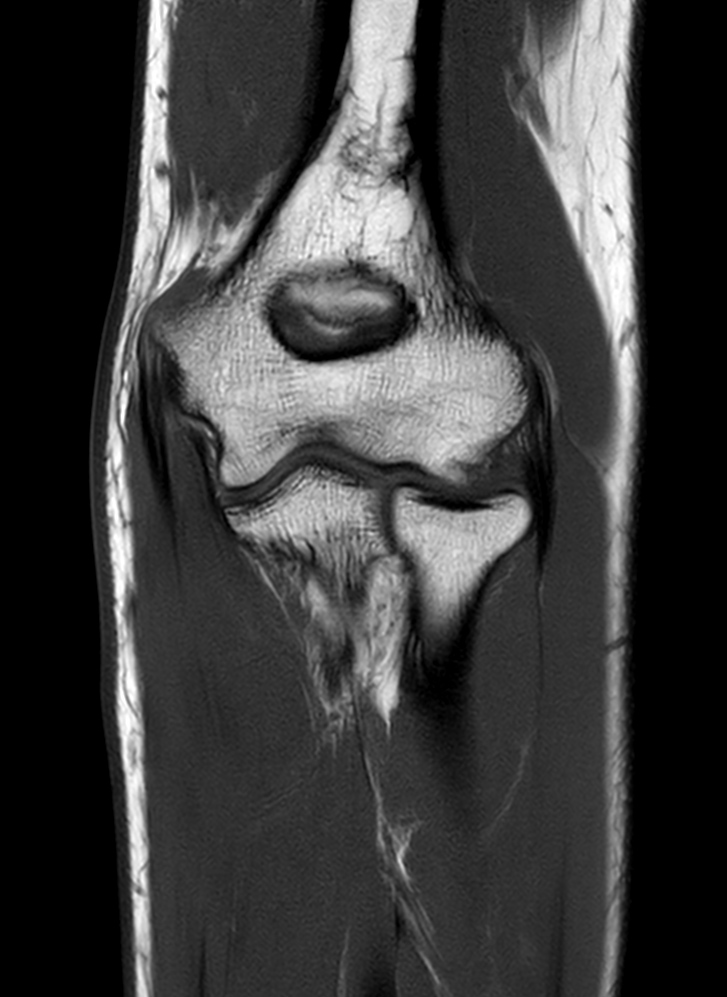

High quality Elbow imaging with Compressed SENSE

Spital Uster, Switzerland